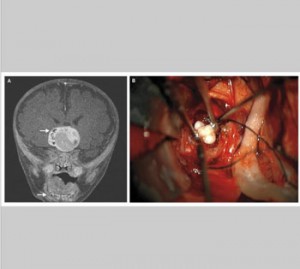

Ad un bambino di 4 anni, durante un controllo pediatrico, si era notato un aumento della circonferenza cranica. La diagnosi un Craniofaringioma Adamantinomatoso, un tumore raro che raggiunge le...